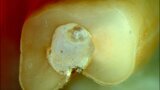

Buccal root of the bifurcated maxillary premolar—a danger zone during root canal therapy